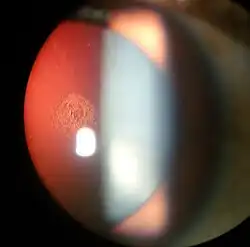

Cortical cataract of a 60-year-old male

Cortical cataract of a 60-year-old male -

Retroillumination of cortical cataract

Retroillumination of cortical cataract -